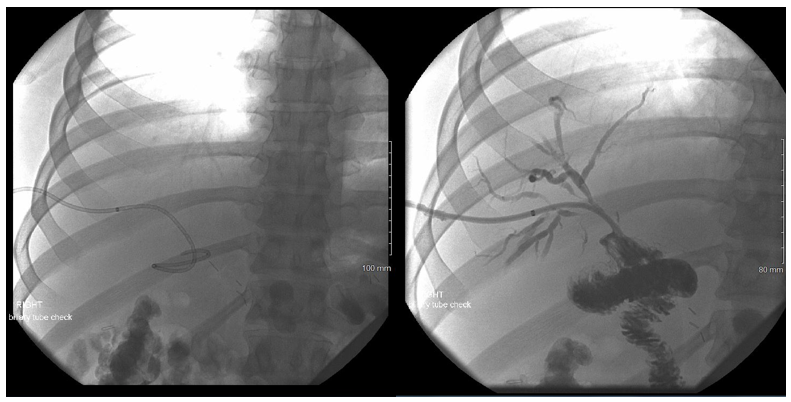

A 29-year-old male presented to an outside hospital for evaluation for abdominal pain and was diagnosed with acute cholecystitis. The patient was taken to the operating room nine days prior to presentation at our hospital for a laparoscopic cholecystectomy. Though the dissection was difficult, the case proceeded uneventfully and the patient was subsequently discharged post-operatively. The patient returned to the outside hospital on post-operative day 7 with high fevers and had a collection seen on ultrasonography, which was then identified as a bile duct leak on HIDA scan. An ERCP was performed at this time, but the biliary duct could not be cannulated due to an obstruction. The patient was brought back to the operating at this point for an exploratory laparotomy. After exploration, the surgeons identified a bile leak, but could not identify the proximal bile duct. Intra-operative cholangiogram was performed through the distal duct, which revealed flow into the duodenum, but the proximal duct could not be identified. Given the complexity of the anatomy and the case, the patient was transferred to us for further surgical management. On arrival, the intraoperative cholangiogram from the outside hospital was reviewed and a diagnosis of congenital agenesis of the common bile duct as suspected as flow through the ligated cystic duct went directly into the duodenum. At this time, Interventional Radiology (IR) was consulted to perform at PTC to review the biliary anatomy and create a road map for further repair. However, only the right hepatic system could be catheterized as the left hepatic duct was too small (Figure 2a). The cholangiogram through the right PTC showed a large bile leak, but no extra-hepatic ducts could be identified at all. Given these findings, the patient was then taken to the operating room for exploratory laparotomy. Upon examining the surgical site, the distal bile duct was significantly dilated to 9-10 millimeters in diameter. Proximally, the right PTC catheter placed by IR was emerging from the intra-hepatic right biliary system and further exploration did not reveal any intra-hepatic biliary ducts from the left or any extra-hepatic ducts. A complete portahepatis lymphadenectomy and dissection with skeletonized hepatic artery and portal vein was performed in an attempt to localize the left intra-hepatic duct and right extra-hepatic duct to no avail. It was suspected that the patient had variant anatomy with common bile duct agenesis with the left hepatic duct connecting to the right hepatic duct high in the liver parenchyma. Given this, continuity was restored to the biliary tree via a hepaticoportal enterotomy, or Kasai procedure. The tissue around the porta hepatis and the right PTC wrapped around an enterotomy in a two layer anastomosis. The patient was managed for the first three post-operative days in the intensive care unit before being transferred to the surgical floors where his recovery continued before ultimately being discharged. Subsequent follow-up appointments revealed adequate patency of the right-sided biliary catheters and ultimately, dilation of the left sided biliary system to permit cannulation and drainage into the intact hepaticoportal enterostomy (Figure 2b and 2c). Clinically, the patient remains stable and with unremarkable laboratory results 18 months from surgery.

The biliary tree has embryological roots as the most caudal portion of the foregut and arises from what is known as the hepatic diverticulum. This divides into two parts, the liver and gallbladder, with the cells in between developing into the cystic and bile ducts to form the fully developed biliary tree that enters the duodenum [6]. The variations in anatomy arise during this stage of development and can arise in any of the involved structures. In terms of the hepaticocystic duct, it is believed that the aberrancy occurs secondary to delayed separation of the hepatic and cystic tissues, persistence of fetal communications, or failure of the cells of the common bile duct to proliferate or recannalize [1,5]. Thus, the gallbladder and cystic duct are interpositioned between the hepatic ducts and the duodenum as the only common channel for biliary outflow. With regards to biliary tree aberrancies, the hepaticocystic duct appears to be the rarest of all anomalies, which can include duplicated structures, anomalous insertions, and congenital agenesis. In a review of the literature, there have only been 25 reports of varying detail of this developmental abnormality in the world as far as we are aware (Table 1) [7-24]. Of these cases, multiple variants have been described with different insertions of the hepatic ducts into the gallbladder with the common link between all of them being the agenesis of the CBD and the solitary outflow of the entire biliary track being provided by the cystic duct into the duodenum [25-31]. This classification system was first described by Losanoff et al. and consists of four types (Figure 3). In Type I, each hepatic duct inserts into the gallbladder separately. Type II results in the joining of the hepatic ducts when they enter the gallbladder. Type III has multiple variants based on where the insertion of the common hepatic duct enters the gallbladder. Type IIIa inserts in the superior portion of the gallbladder wall, IIIb into the neck of the gallbladder, IIIc into the posterior wall of the gallbladder, and IIId into the gallbladder fundus. The type IV variant has multiple individual ducts draining the liver inserting into the wall of the gallbladder [3]. In our first patient, we observed the Type IIId variant of the hepaticocystic duct whereas the second did not appear to match any of Losanoff’s classifications. Presentation of extra-hepatic biliary tree abnormalities can be hard to diagnose and distinguish pre-operatively from normal anatomy. Often, pathology presents with symptoms of RUQ pain, jaundice, nausea, vomiting or fevers with laboratory findings of leukocytosis or elevated liver enzymes, all of which may be due to cholelithiasis, choledocholithiasis, cholangitis, or hepatic pathology [3,5,15,16,20-24]. Work-up may include RUQ ultrasounds, computed tomography (CT), magnetic resonance imaging (MRI), or radioactive nucleotide studies such as the HIDA scan. Of these, abnormalities would most likely be discovered on HIDA as flow of the nucleotide is observed through the biliary tree, though CT or MRI may also reveal anatomic variations. However, workup is usually limited to RUQ ultrasound in the correct clinical setting for gallbladder disease before operative management may be indicated, which is what occurred in our two cases [17,19]. Thus, diagnoses of biliary tree aberrancies are generally not obtained until operative exploration or intraoperative cholangiogram for unclear anatomy [3,20,25]. Our first patient’s anatomy was initially noted when there was persistent bile leak noted from a duct near the fundus of the gallbladder and subsequent porta hepatis exploration and intraoperative cholangiogram. Imaging highlighting the proximal left and right hepatic duct and the transected cystic duct leading to the duodenum from Case 2 is shown in Figure 2a-2c. Consequences of an unrecognized biliary duct abnormality could be catastrophic, leading to significant morbidity and mortality. With anomalous hepatic ducts inserting at various locations on the gallbladder, ligation is essentially guaranteed while performing a cholecystectomy, especially if the surgeon is unaware of their presence [26]. While small caliber ducts may be ligated without any complications, accessory ducts with large lumens can cause significant leakage of bile, infection, or poor nutrient absorption. Severe consequences include formation of sub-phrenic abscesses, cirrhosis, external biliary fistulas, frank peritonitis, and even death [4,6,21,27]. When hepaticocystic ducts are diagnosed, various management strategies can be employed depending on when duct anatomy is discovered. When identified prior to removal of the gallbladder, a planned partial cholecystectomy could be performed with a choledochoplasty to preserve the biliary outflow into the duodenum through to remnant cystic duct [15,19-20,22]. If the cholecystectomy has already been completed, leaving behind a one or more proximal hepatic duct stumps and the distal cystic duct stump, primary anastomosis can be performed or a Roux-en-Y hepaticojejunostomy can be used to achieve adequate elimination of bile [5,15,19,21]. Primary anastomosis should only be attempted if is not a significant defect resulting from the cholecystectomy, if there will be anastamotic tension, or if there will not be high risk of biliary stricture [16,19,21]. The distance between our hepatic stump and cystic duct stump after cholecystectomy in Case 1 was approximately 3cm and had too large of a defect to perform a primary anastomosis. No discernible left hepatic duct could be found radiographically or on surgical exploration in Case 2. Thus, we opted for a Roux-en-Y hepaticojejunostomy to re-establish continuity to the biliary tree in Case 1 and a hepaticoporto enterostomy in Case 2 given the anatomical remnants post-cholecystectomy in each of the patients. The patients did not experience any complications from the surgeries and both remain well post-operatively.